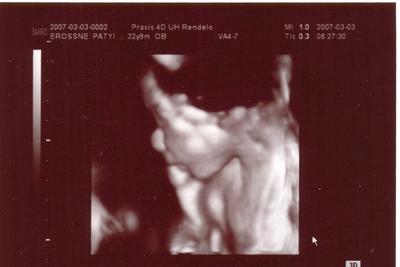

[quote="emma1976"]J írta:emma1976ól értettelek titeket: UH-val megnézik a méhszájat? Mert mióta hallottam tőletek, hogy csak úgy kinyílhat, azon gondolkodtam, hogy ezt kézzel látják, vagy hogyan, hogy már nem okés?